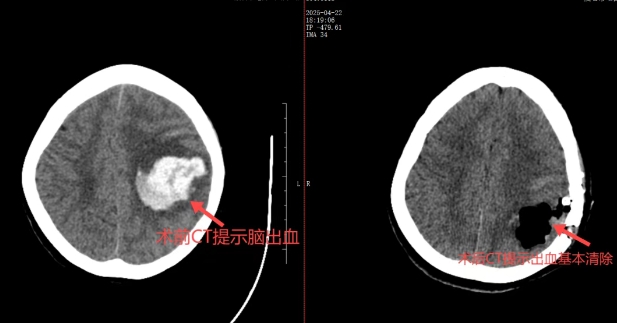

患者王女士因左顳葉腦出血(30 毫升)陷入深度昏迷,入院時(shí) GCS 評(píng)分僅 6 分。得益于 “五級(jí)” 聯(lián)動(dòng)機(jī)制下暢通的急救網(wǎng)絡(luò),梁海波主任團(tuán)隊(duì)迅速啟動(dòng)綠色通道,結(jié)合 CT 三維重建精準(zhǔn)定位病灶。在省醫(yī)專(zhuān)家的協(xié)同支持下,果斷采用神經(jīng)內(nèi)鏡微創(chuàng)治療方案。術(shù)中,團(tuán)隊(duì)?wèi){借 5 厘米的微小切口、3 厘米的微骨窗建立操作通道,借助高清內(nèi)鏡清晰視野,精準(zhǔn)清除血腫,并利用雙極電凝實(shí)現(xiàn)毫米級(jí)精細(xì)止血。整臺(tái)手術(shù)僅耗時(shí) 1 個(gè)半小時(shí),全程出血不足 50 毫升。術(shù)后 CT 顯示,血腫清除率高達(dá) 99%,患者次日便恢復(fù)意識(shí),“五級(jí)” 聯(lián)動(dòng)的高效救治能力在此得到充分彰顯。